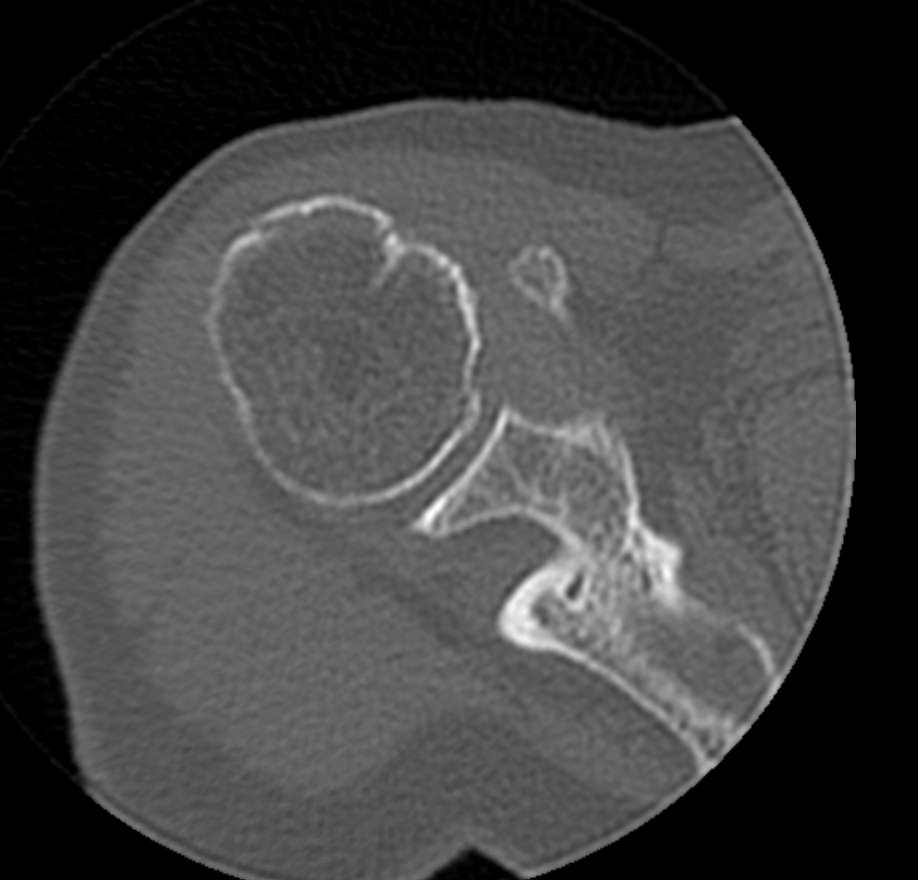

Так как рентгеновские лучи хорошо поглощается костной тканью, метод КТ наиболее информативен именно для обследования костных структур. Кроме того, компьютерная томография отличается быстротой, безболезненностью и неинвазивностью (то есть не требует вмешательства в организм человека). Поэтому методика, в первую очередь, применяется для диагностики травматических повреждений – различных переломов, вывихов и подвывихов плечевого сустава.

В случае необходимости проведения оперативного вмешательства КТ дает исчерпывающую информацию о расположении костных отломков, а после операции позволяет оценить правильность репозиции фрагментов кости и состояние эндопротеза.

Что показывает КТ плечевого сустава

- трещины, переломы (в т. ч. скрытые),образовавшиеся в полости сустава или в прилегающих тканях гематомы;

- остиомиелит, некроз головки плечевой кости;

- дегенеративные изменения: остеохондропатии, остеоартрозы, артрозы;